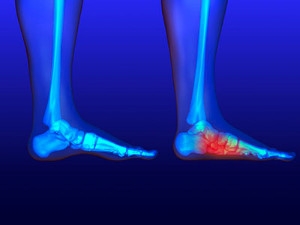

The plantar fascia is a connective tissue in the heel that stretches across the bottom length of your foot. Plantar fasciitis occurs when the connective tissue becomes inflamed, causing heel pain and discomfort during physical activity. Although the condition is completely treatable, traditional methods can take up to a year to start becoming effective.

Plantar fasciitis is caused by a number of everyday activities, so understanding the condition is important for managing and treating it. One of the most common causes of plantar fasciitis is excessive running, especially with improper fitting or non-supportive shoes. Too much exercise can lead to the plantar fascia being overworked and overstretched, which can cause tears in the tissue. Along with improper fitting shoes, pronation, the rolling of the feet inward, is a common cause of plantar fasciitis. If not treated properly, the plantar fascia becomes overstretched and starts to tear, causing inflammation.

Causes of Heel Pain

Heel pain can be debilitating and can form due to a variety of reasons. The most common cause of heel pain occurs when the band of tissue that connects the heel bone to the toes, known as the plantar fascia, becomes inflamed causing plantar fasciitis. When the Achilles tendon becomes inflamed Achilles tendonitis may occur, and this can lead to heel pain too. Heel pain can also be caused by a natural wearing of the fat pad which is connected to the heel, as well as stress fractures, bursitis, or a variety of diseases such as arthritis and gout. If you are suffering from heel pain it is highly recommended that you visit a podiatrist who can determine what the cause of your pain is. A podiatrist will be able to provide a proper treatment plan for your heel pain as well.

Heel pain can be debilitating and can form due to a variety of reasons. The most common cause of heel pain occurs when the band of tissue that connects the heel bone to the toes, known as the plantar fascia, becomes inflamed causing plantar fasciitis. When the Achilles tendon becomes inflamed Achilles tendonitis may occur, and this can lead to heel pain too. Heel pain can also be caused by a natural wearing of the fat pad which is connected to the heel, as well as stress fractures, bursitis, or a variety of diseases such as arthritis and gout. If you are suffering from heel pain it is highly recommended that you visit a podiatrist who can determine what the cause of your pain is. A podiatrist will be able to provide a proper treatment plan for your heel pain as well.

Heel pain is often associated with plantar fasciitis. The plantar fascia is a band of tissues that extends along the bottom of the foot. A rip or tear in this ligament can cause inflammation of the tissue.

Heel spurs are another cause of pain. When the tissues of the plantar fascia undergo a great deal of stress, it can lead to ligament separation from the heel bone, causing heel spurs.

The plantar fascia is the fibrous tissue that runs along the bottom of the foot and connects to the heel bone. When the plantar fascia becomes inflamed due to overstretching, plantar fasciitis occurs and usually results in heel pain, heel spurs, or arch pain. Pain is often felt on the inside of the foot where the heel and arch meet, and it is at its worst in the mornings or after a long rest. Flat feet is the leading cause of plantar fasciitis because the plantar fascia gets stretched away from the heel when bearing weight. When flat feet are the cause of plantar fasciitis, orthotics that support the arch will likely be needed for treatment. Since plantar fasciitis has other causes, patients who believe that they have it should consult with a podiatrist to find the cause and a proper treatment method.

The plantar fascia is the fibrous tissue that runs along the bottom of the foot and connects to the heel bone. When the plantar fascia becomes inflamed due to overstretching, plantar fasciitis occurs and usually results in heel pain, heel spurs, or arch pain. Pain is often felt on the inside of the foot where the heel and arch meet, and it is at its worst in the mornings or after a long rest. Flat feet is the leading cause of plantar fasciitis because the plantar fascia gets stretched away from the heel when bearing weight. When flat feet are the cause of plantar fasciitis, orthotics that support the arch will likely be needed for treatment. Since plantar fasciitis has other causes, patients who believe that they have it should consult with a podiatrist to find the cause and a proper treatment method.

What Is Plantar Fasciitis?

Plantar fasciitis is the inflammation of the thick band of tissue that runs along the bottom of your foot, known as the plantar fascia, and causes mild to severe heel pain.

The plantar fascia is a connective tissue in the heel that stretches across the bottom length of your foot. Plantar fasciitis occurs when the connective tissue becomes inflamed, causing heel pain and discomfort during physical activity. Although the condition is completely treatable, traditional methods can take up to a year to start becoming effective.

Plantar fasciitis is caused by a number of everyday activities, so understanding the condition is important for managing and treating it. One of the most common causes of plantar fasciitis is excessive running, especially with improper fitting or non-supportive shoes. Too much exercise can lead to the plantar fascia being overworked and overstretched, which can cause tears in the tissue. Along with improper fitting shoes, pronation, the rolling of the feet inward, is a common cause of plantar fasciitis. If not treated properly, the plantar fascia becomes overstretched and starts to tear, causing inflammation.